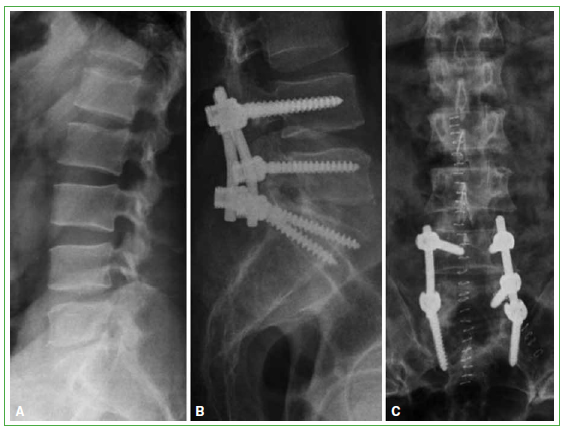

Figura 2.

Tomografía computarizada de columna lumbar. A. Corte lateral. Lesiones líticas en la placa superior y el cuerpo de L3 y L4. B. Corte coronal. Lesiones líticas en la placa superior y el cuerpo de L3 y L4. C. Radiografía de columna lumbar lateral. Se observa el resultado de la instrumentación lumbar larga de T12-L1-L2-L5 y S1, realizada en noviembre de 2012.

En controles seriados, se detecta colapso vertebral de L2, L3 y L4, además de quistes hidatídicos en el músculo psoas ilíaco, por lo que se decide realizar una instrumentación posterior larga. En noviembre de 2012, se procede a una fijación posterior de T12-L5 con tornillos pediculares y a una laminectomía amplia de L3-L4 (Figura 2).